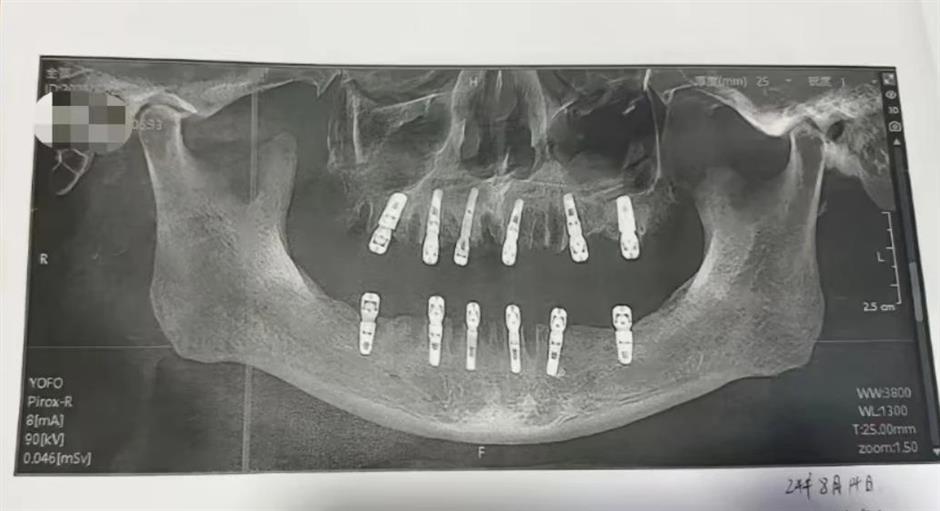

في واقعة غريبة من نوعها ، لقي رجل مسن حتفه بعد خلع 23 سنًا وزرع 12 سنًا جديدة في نفس اليوم في عيادة أسنان في تشجيانغ الصينية .

وأوضحت ابنة المسن في تصريحات إعلامية أن والدها عانى من آلام مبرحة طوال الـ13 الأخيرة من حياته بعد عملية خلع وزراعة الأسنان ، قبل أن يعاني من نوبة قلبية أدت إلى وفاته